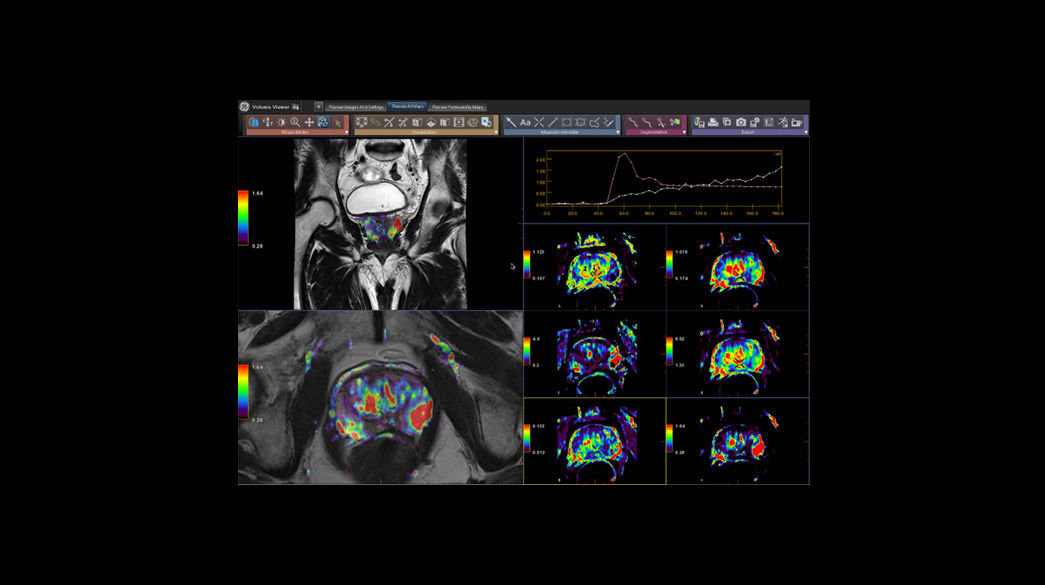

Quantifiable

Provides quantitative and actionable information

Precision and personalization

MR-Advanced-Visualization1040-x-585